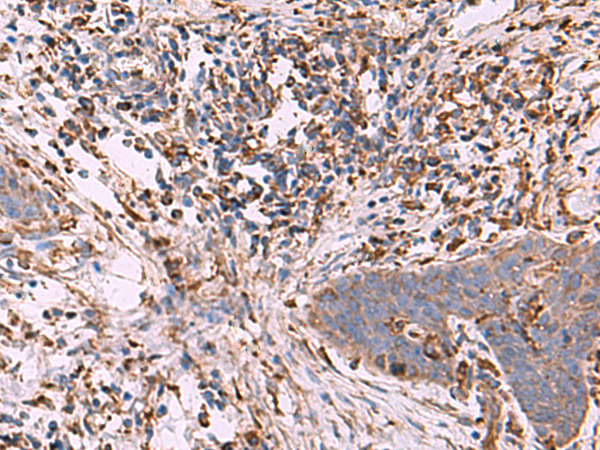

The image is immunohistochemistry of paraffin-embedded Human cervical cancer tissue using P13685(G6PC1 Antibody) at dilution 1/70. (Original magnification: ×200) |

The image is immunohistochemistry of paraffin-embedded Human esophagus cancer tissue using P13685(G6PC1 Antibody) at dilution 1/70. (Original magnification: ×200) |